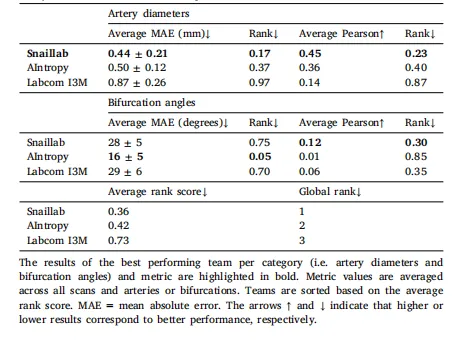

Table 3Results and ranking of proposed solutions by each team for Task 2 (quantification ofartery diameters and bifurcation angles) on the test set.

表3 各团队针对任务2(动脉直径和分叉角度量化)在测试集上提出的解决方案的结果及排名